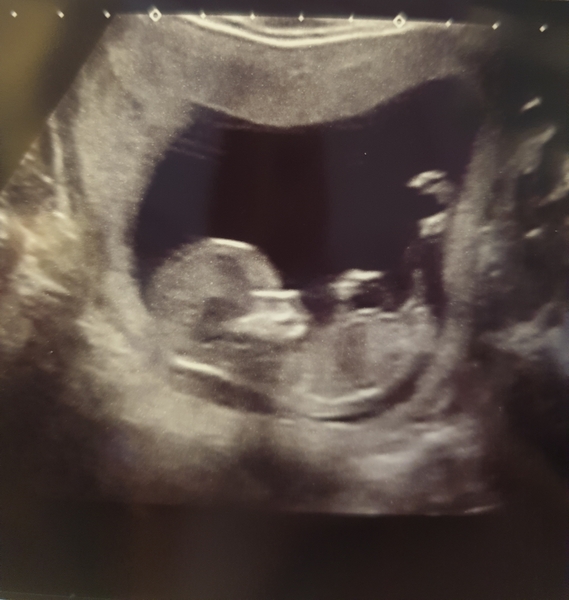

Had my dating scan today and all is looking good. Baby was wriggling around like mad, which was lovely to see but have the sonogropher a tough job. Also got to hear the heartbeat and promptly burst into tears. What an amazing experience. My adjusted EDD is now 14 Jan 2020, so 6 days earlier than originally thought.

Lovely photos @Chips84

My dating scan today too!! I'm due 15th Jan. It was the most amazing experience. Baby was not playing ball and had to jump around to get it in position and then was sent for a walk!!

Great scan pictures today!

Great scan pics! Grin

Wonderful scan pictures ladies, amazing how they're all unique !